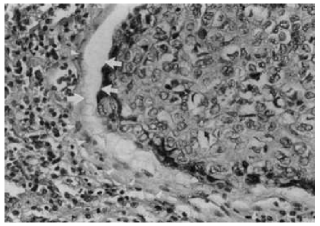

The structure and dynamics of the tumor-host interface in invasive cancers are controlled by the same parameters which generate a transformation from a benign tumor into malignant tumor. A hypo-cellular interstitial space, as we can see in Figure 1 [7, Figure 4a], occurs in some cancers.